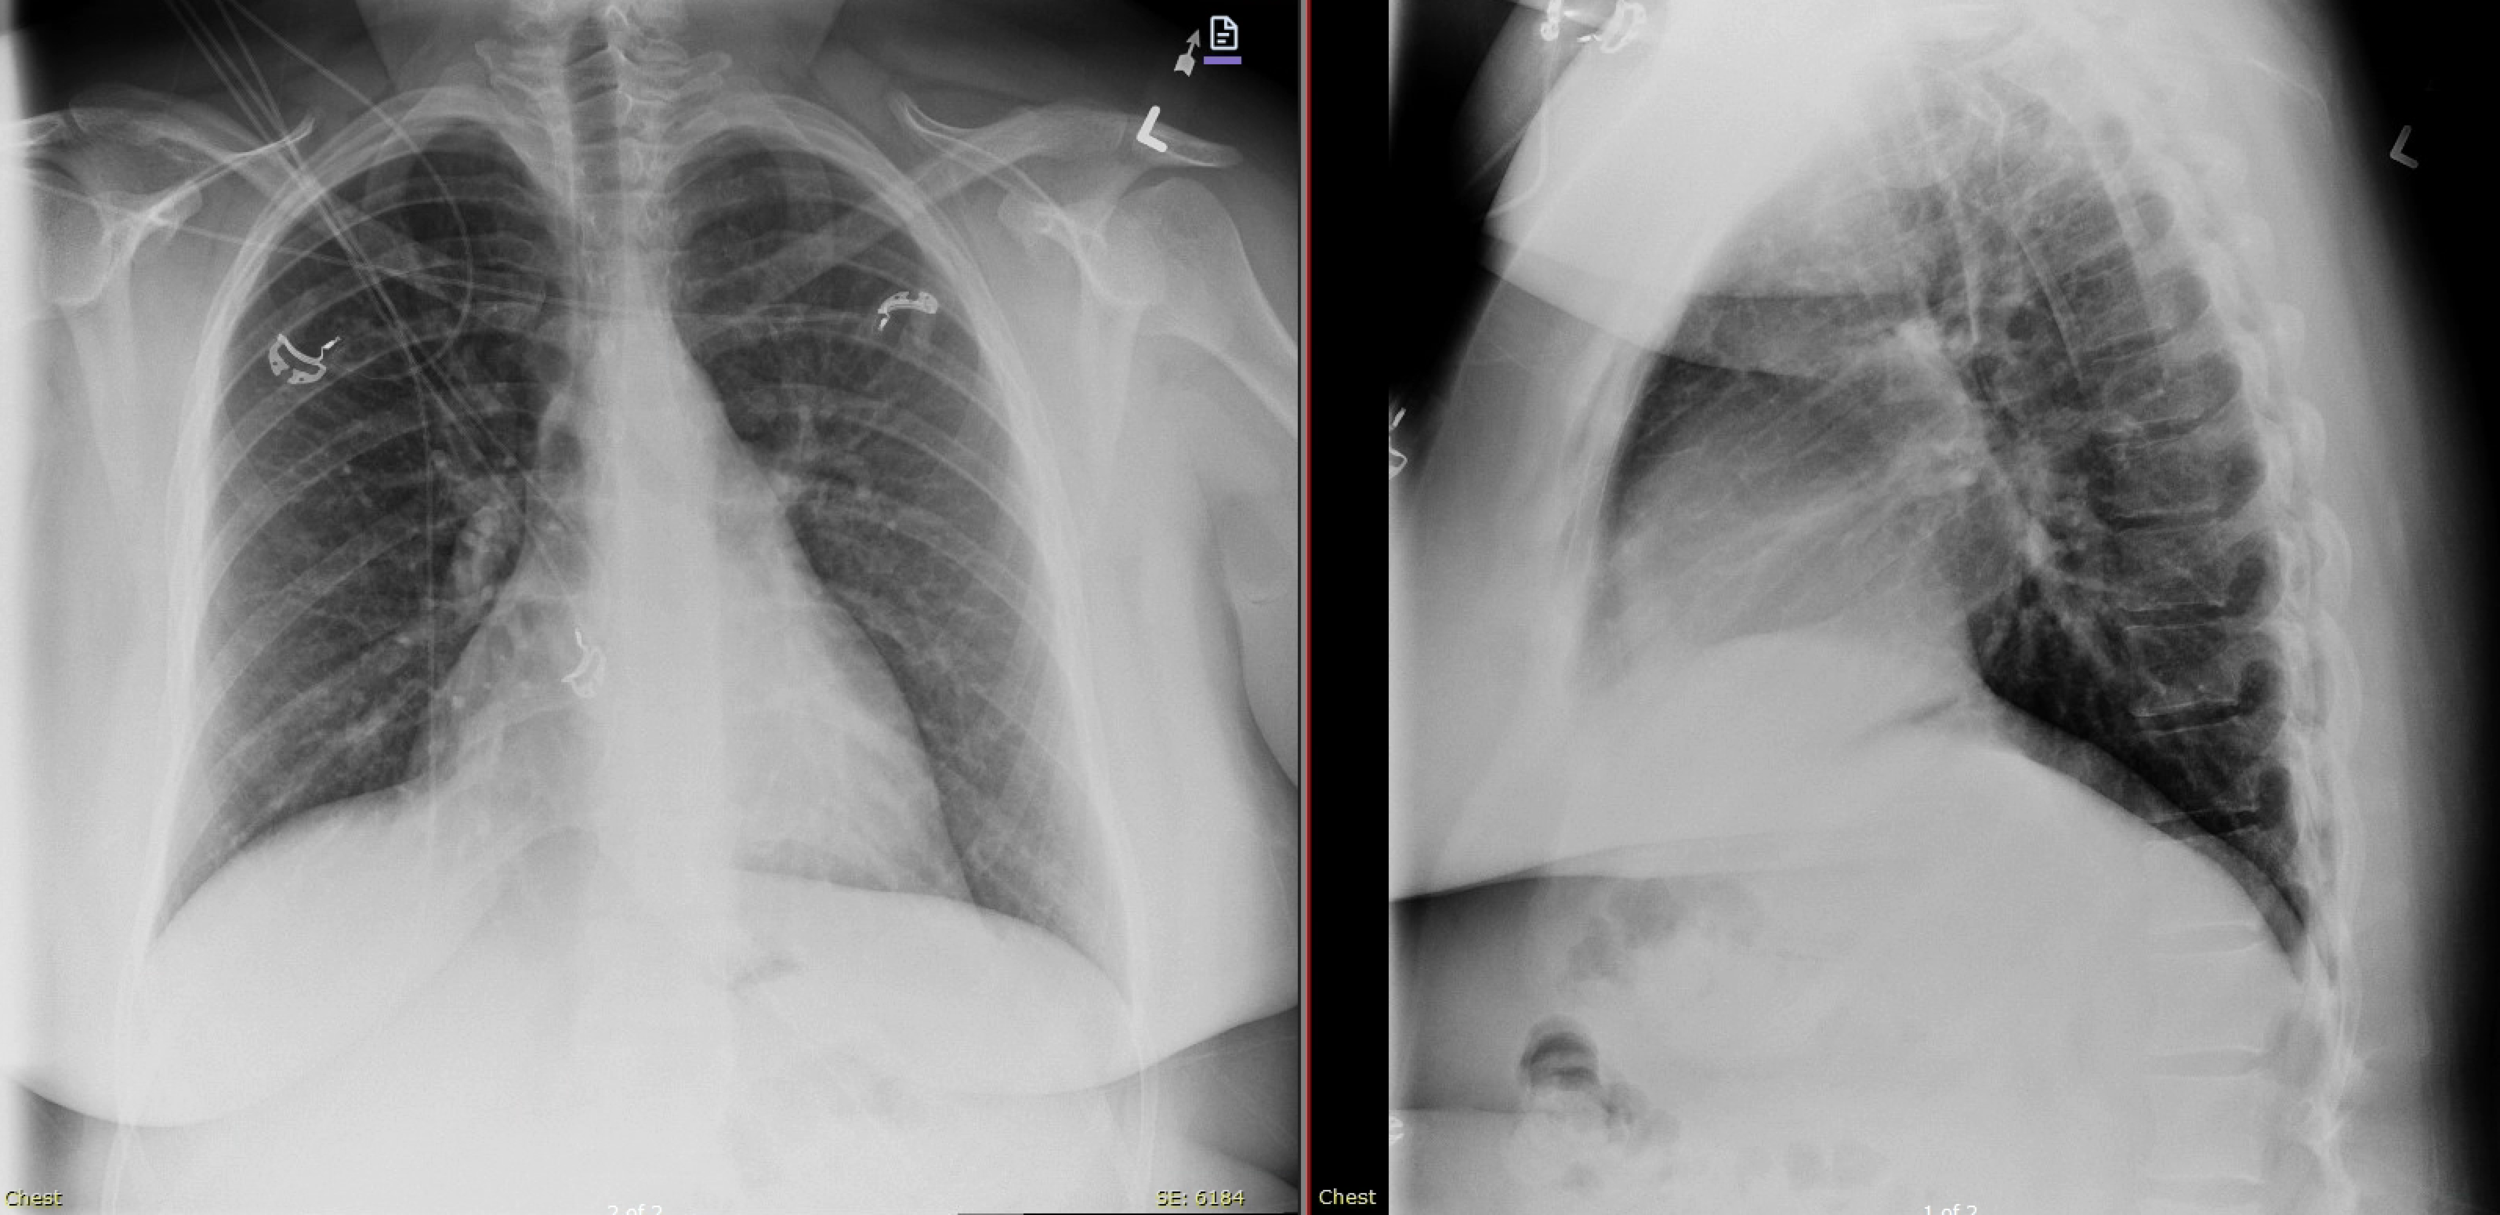

CXR